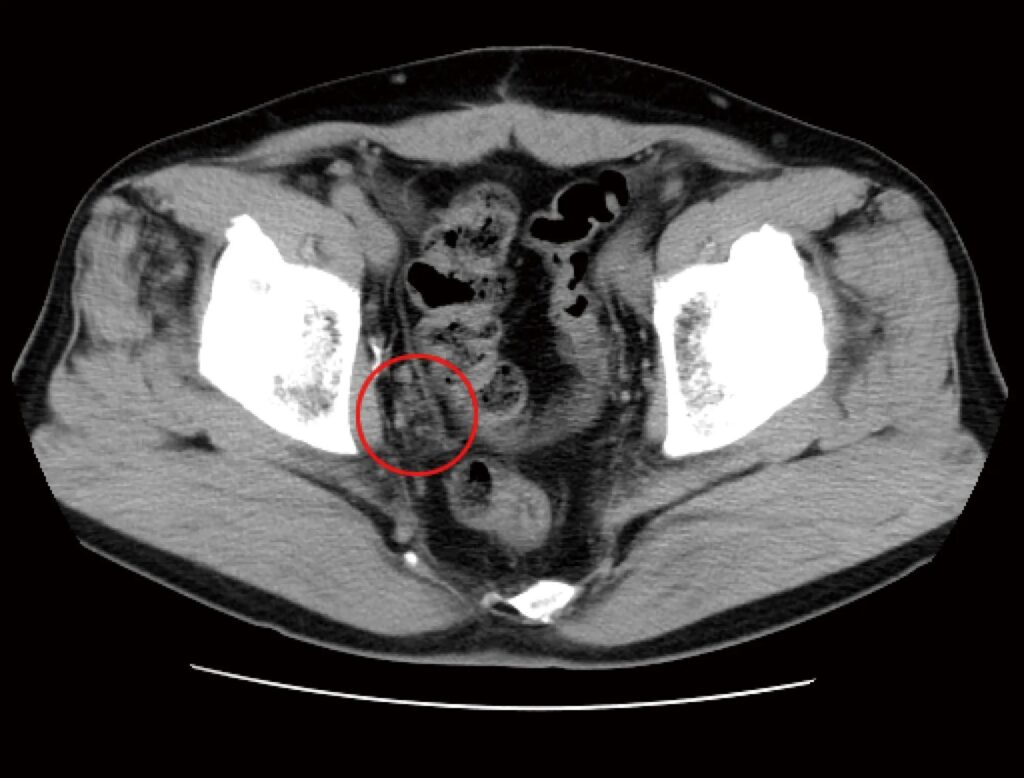

治療前のCT検査結果

免疫治療前に拝見したCT検査によると、骨盤の底部/右側(写真では左・赤マル部分)を中心に、複数のリンパ節転移によって形成されたがん病巣が認められました。